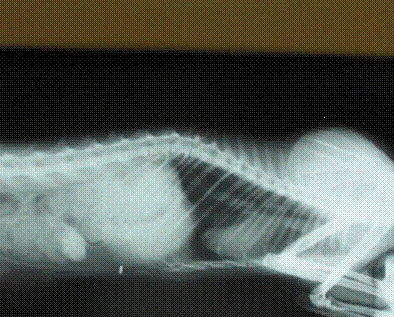

Рис. 8. Через сутки после операции (видно

продвижение сульфата бария).